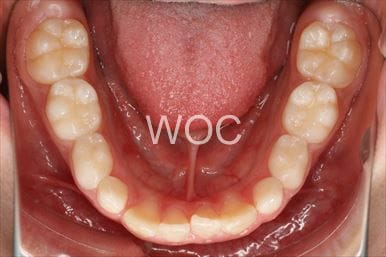

治療前1

治療前2

治療前3

治療前4

治療前5